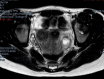

Figure 1

MRI T1‐Weighted Axial Image Demonstrates a Hyperintense Cystic Lesion in the Myometrium.